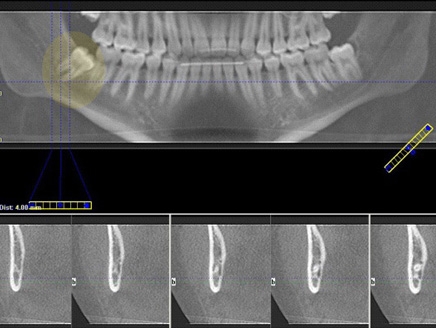

وتعتمد نسبة انتشار الورم على سن المريض وعلى نوع الصورة الإشعاعية بما أن الأشعة السينية تستعمل بطرق مختلفة.